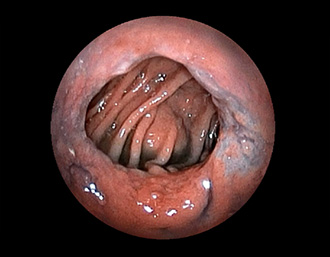

症例1:胃潰瘍(37才、男性)

①胃潰瘍(Stage A1)

健診:胃レントゲン検査で、胃角部ニッシェを指摘され当院受診。

胃角部小弯に、深くて大きな、大きさ約10mmの胃潰瘍(stage 1)

があり、潰瘍底は一部白苔はみ出しを認める。エソメプラゾールマグネシウム水和物投薬で治療開始しました。

(通常画像)